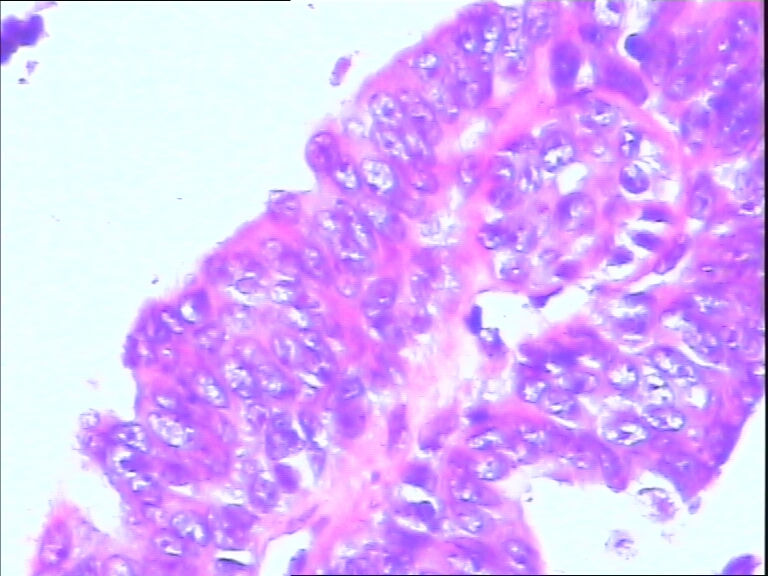

B3785左乳头包块!

42y

左乳头有3mm结节

灰白不整形组织一块:0.7*0.5*0.4

• 左乳头包块!图1

图1

标签:导管内乳头状肿瘤

诊断导管内乳头状瘤.做免疫组化肌上皮标记,排除癌变

导管内乳头状瘤

导管内乳头状瘤,导管上皮不典型增生。

乳头腺瘤(nipple duct adenoma)或称乳头的乳头状瘤

导管内乳头状瘤,局灶伴不典型增生。

导管内乳头状肿瘤.做免疫组化肌上皮标记,排除癌变。

有异性,考虑导管内乳头状癌

导管内乳头状结构,细胞无异型性,诊断导管内乳头状瘤。